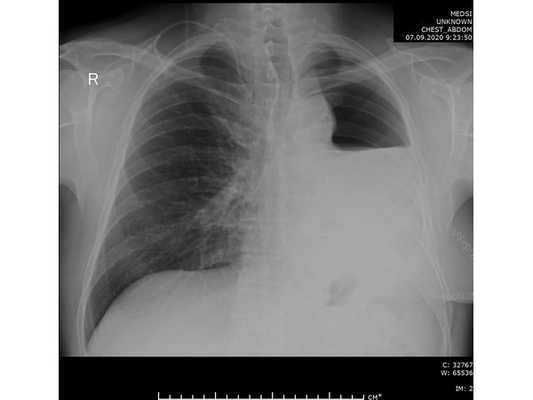

31.07.2020 мужчина 57 лет обратился в Клиническую больницу № 2 АО ГК МЕДСИ с данными компьютерной томографии, где выявлено центральное новообразование в корне нижней доли левого лёгкого.

При дальнейшем дообследовании, по данным рентгенографии и компьютерной томографии органов грудной клетки выявлено новообразование в нижней доле левого лёгкого. После этого пациент был направлен на консультацию к торакальному онкологу.

Чтобы провести первичное стадирование опухоли, пациенту проведена позитронно-эмиссионная томография в сочетании с компьютерной томографией (ПЭТ-КТ). По данным исследования, выявлена метаболически активная опухоль в корне левого лёгкого с бугристыми контурами размерами 41 х 43 мм. В толще опухоли проходят нижнедолевой бронх и бронх 6-го сегмента левого лёгкого, просветы бронхов значительно сужены. Нижняя доля левого лёгкого уменьшена в размерах за счёт того, что сегменты 6, 9 и 10 субтотально (частично) инфильтрированы и безвоздушны. Лимфатические узлы корня лёгкого и средостения не увеличены в размерах и не накапливают радиофармпрепарат (РФП), который был введён пациенту перед обследованием внутривенно. Других очаговых образований и очагов гиперметаболизма в организме не обнаружено.

При этом отмечено, что опухоль распространяется в средостение по нижней стенке левого главного бронха и широко прилежит к нижнегрудному отделу аорты (по заключению специалиста ПЭТ-КТ — имеется инвазия опухоли в ткани средостения и возможное врастание в стенку аорты). При самостоятельном пересмотре изображений отмечено, что "опухолевая" ткань, которая распространяется по нижней стенке левого главного бронха в средостение, не накапливает РФП (т. е. не является злокачественной), а стенка аорты в области "инвазии" опухоли имеет ровный чёткий контур и адвентициальную границу, что также свидетельствует об отсутствии онкологического процесса в этой области.

Основное заболевание: Центральный немелкоклеточный рак нижней доли левого лёгкого, сT2bN0M0, IIА стадия. (T2b — опухоль более 5 см, но менее 7 см в наибольшем измерении; N0 — нет метастазов в региональных лимфатических узлах; M0 — нет отдалённых метастазов).

Проведена профилактическая стандартная антибактериальная терапия в течение пяти суток. По данным контрольной рентгенографии, отмечено смещение средостения в оперированную сторону.